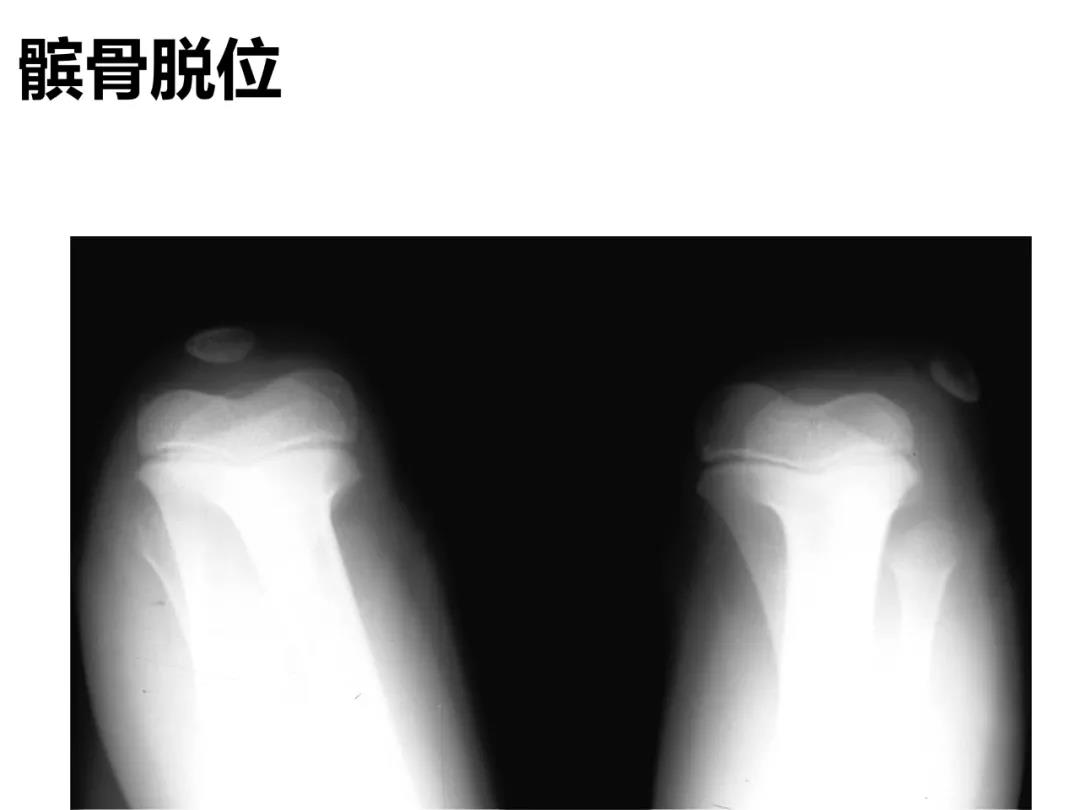

小儿骨科X线片汇总,临床读片宝典!